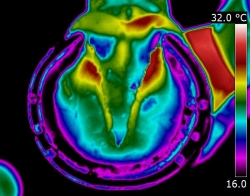

| DISTAL LIMB

| Thermography can point to potential conditions through changes in heat patterns, before the horse shows any clinical signs of injury. It can also reveal hidden signs that other diagnostic tools cannot. It gives us information we didn't know, we didn't know.

| | |  | | | I am very interested in the distal limb and thermography can be used to provide

you and your professional team additional information about conditions such as navicular syndrome,

laminitis, abscesses and corns. Importantly, it can give us information regarding hoof balance and weight-bearing. Hoof balance, often over looked, is a significant influence in the cause of lameness problems not only locally in the foot but throughout the musculature of the body through compensatory issues.